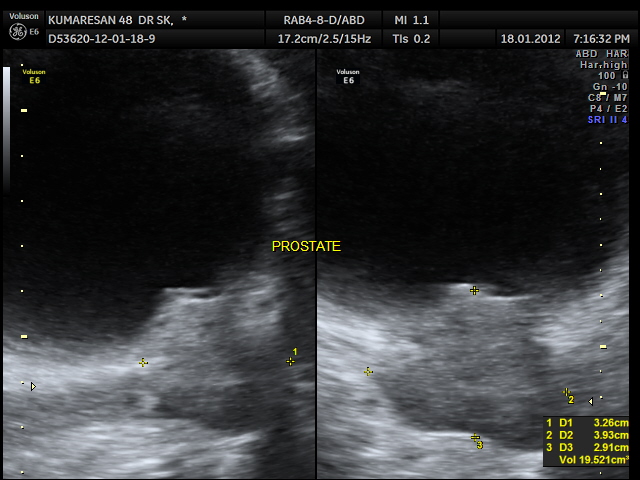

the median lobe prominence is well appreciated in the 2 d image also.